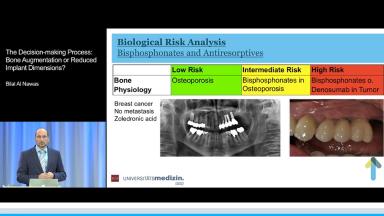

Bone augmentation is an important tool towards achieving a favorable implant prognosis. Complex horizontal and vertical augmentations carry a risk of early and late biological complications. At the same time, a reduced implant diameter and implant length might allow the safe insertion of implants into local bone with less invasive or no augmentation. The risk of this approach could be more technical failures in the long term. The decision-making process presented in this lecture involves the patient perspective and discussion of the different alternatives. 3D diagnostics and virtual planning are also discussed; these tools allow bidirectional planning with respect to both the available bone volume and the prosthodontic restoration.